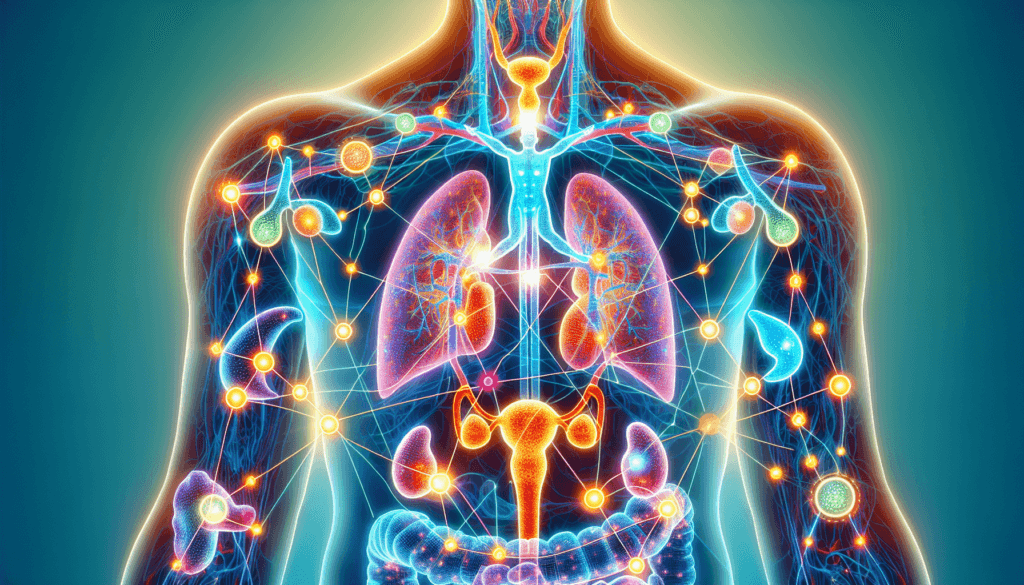

Let’s begin with the basics. Hormones are like the text messages of your body. They carry vital information and instructions from one part of your body to another. However, unlike digital messages that can disappear into cyberspace, these chemical signals have precise destinations and tasks. Produced by glands within your endocrine system, they travel through your bloodstream to organs and tissues, guiding them on how to function efficiently.

You might underestimate these little guys, but consider this: hormones are vital for your growth, metabolism, mood regulation, reproductive health, and even how you respond to stress. Picture hormones as the critical gears and levers in a finely tuned machine. When they work seamlessly, everything runs smoothly. But if there’s a glitch, you may encounter a whole myriad of symptoms and health issues.

It’s time to meet some of the major players in this hormonal chess game. Each hormone has distinctive roles and influences on your overall well-being.